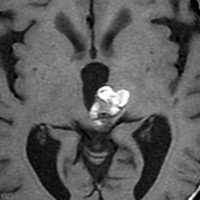

左のMRIで右側脳室三角部というところに,12mm程度の脳室内海綿状血管腫があります。15ヶ月後の画像では顕著に増大しています。脳室内海綿状血管腫は症状を出さなくてもどんどん大きくなってしまうものが多いです。ですから経過観察は頻回にしなければなりません。3ヶ月くらいであっと驚くような大きさになることもあります。